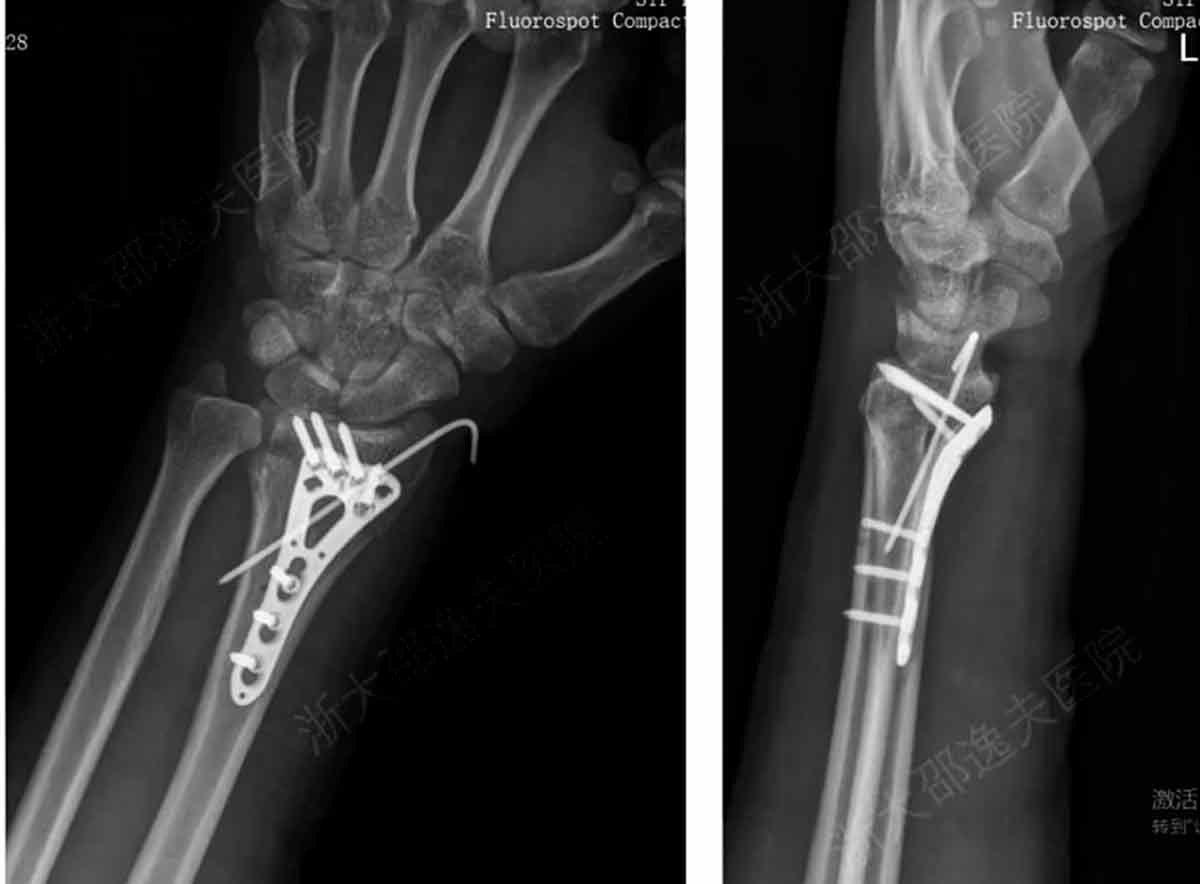

Substituição de placas, pinos e parafusos metálicos

Fim das cirurgias invasivas com implantes metálicos